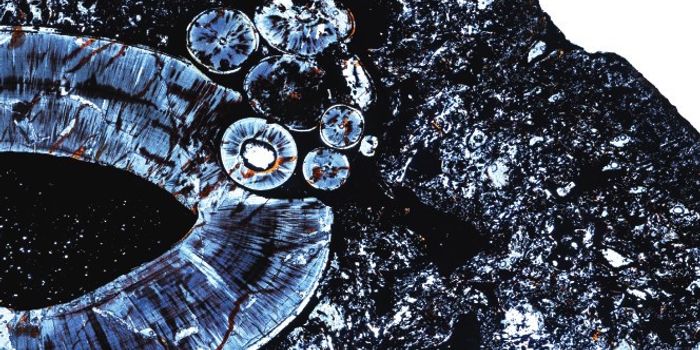

FEB 09, 2024CancerHistopathology describes the process of examining pieces of tissue using a microscope. Light microscopic (LM) exam ...